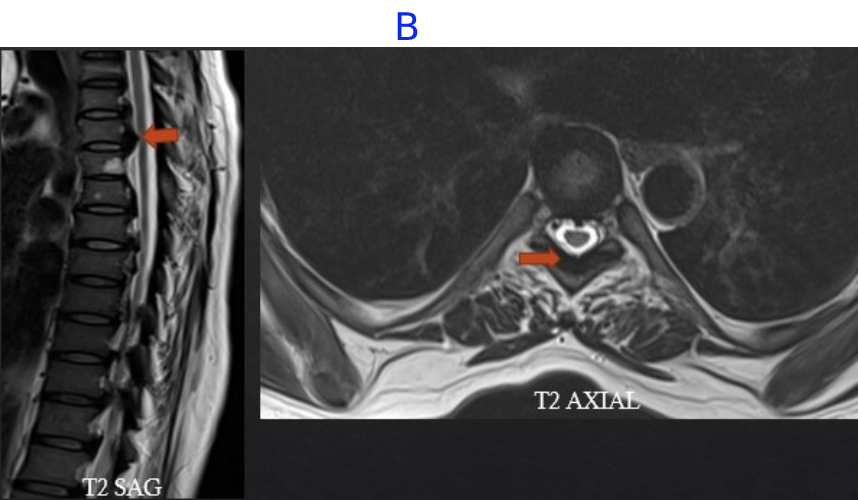

B) LEGENDS

• Multi-focal areas of posterior longitudinal ligament and ligamentum flavum hypertrophy at multiple vertebrae level indenting on the anterior and posterior thecal sac